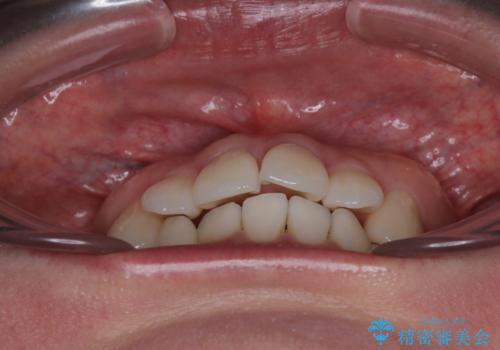

初診時、上下顎ともに歯列の不正が認められ、特に左下の小臼歯が大きく歯列から外れている状態でした。その影響により、下顎の正中が左側へシフトしており、見た目だけでなく噛み合わせにも影響が出ていました。

左下の小臼歯をきれいに歯列内へ並べるためには、まず十分なスペースの確保が必要でした。